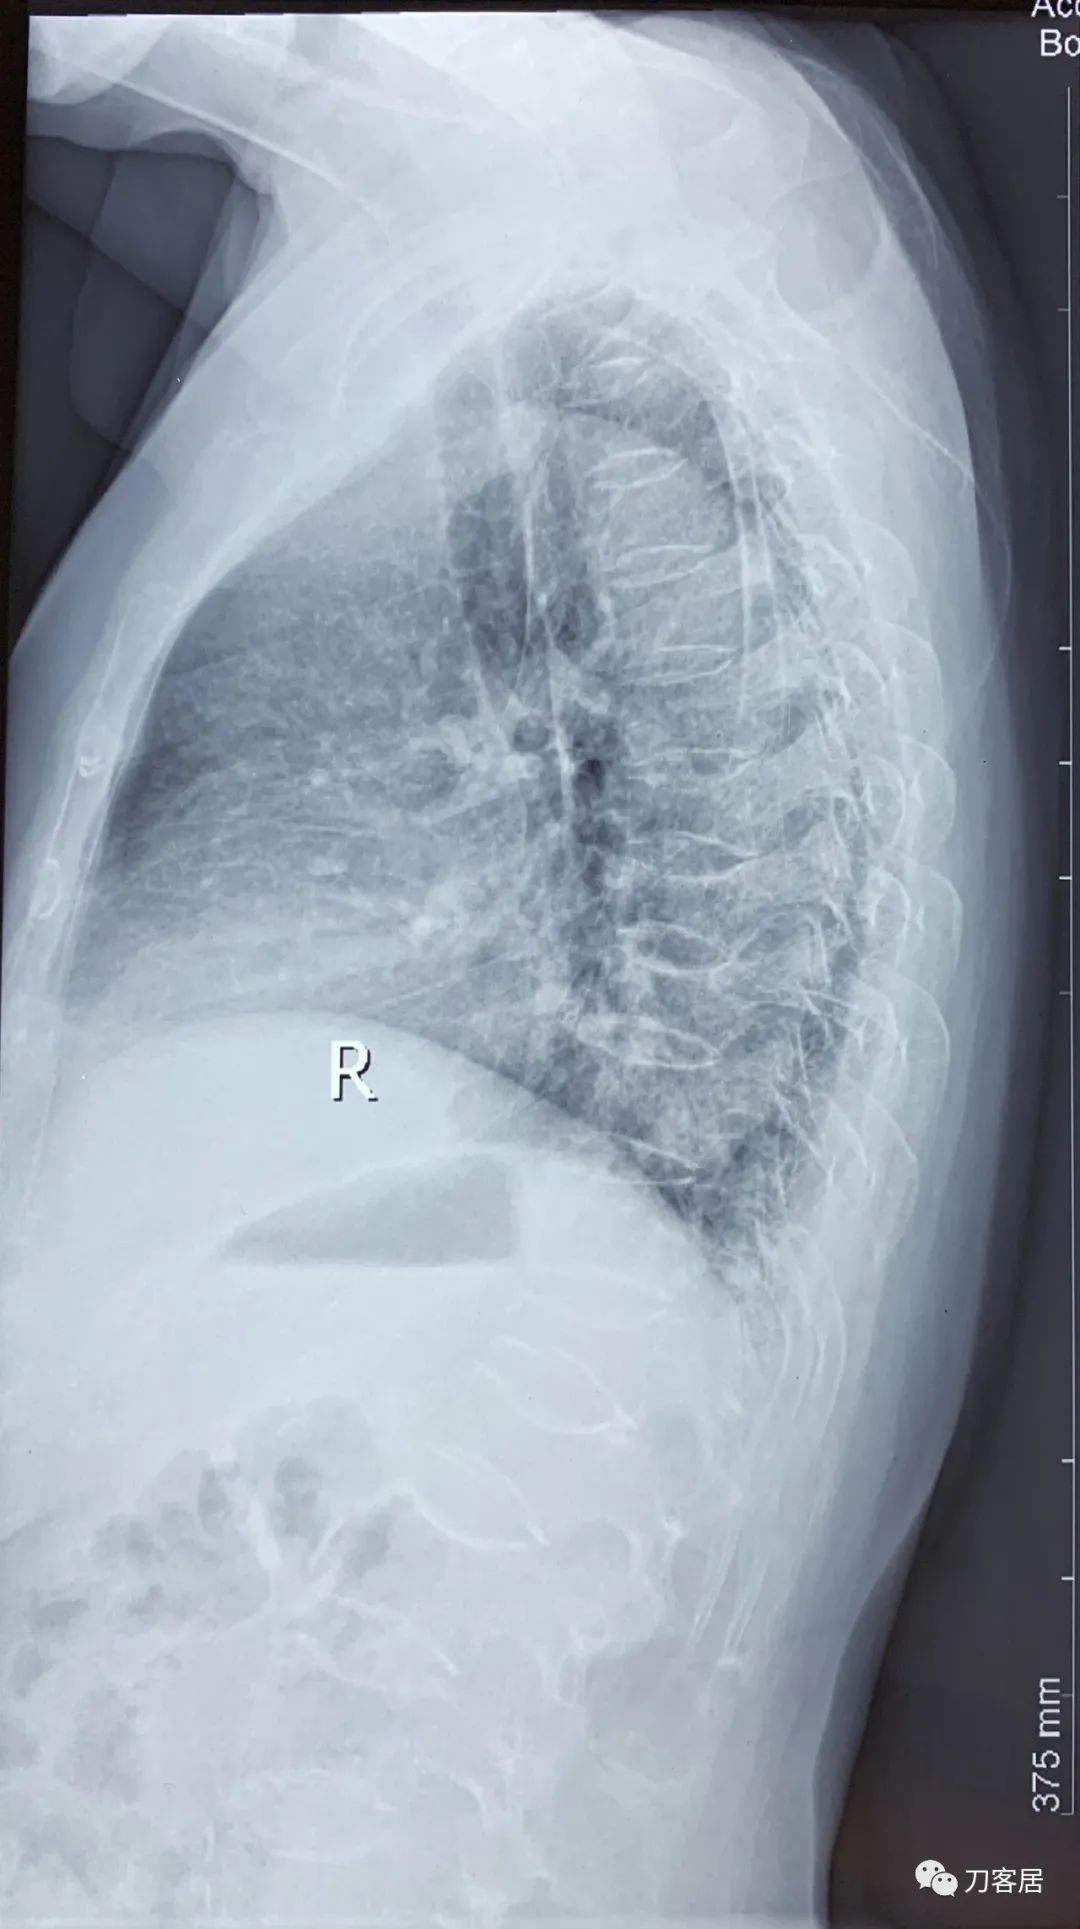

自带影像学资料提示胸椎,腰椎多发脊柱压缩性骨折。

诊断 : 重度骨质疏松症,胸椎、腰椎多发椎体压缩性骨折

图02-20200825胸椎侧位X线片